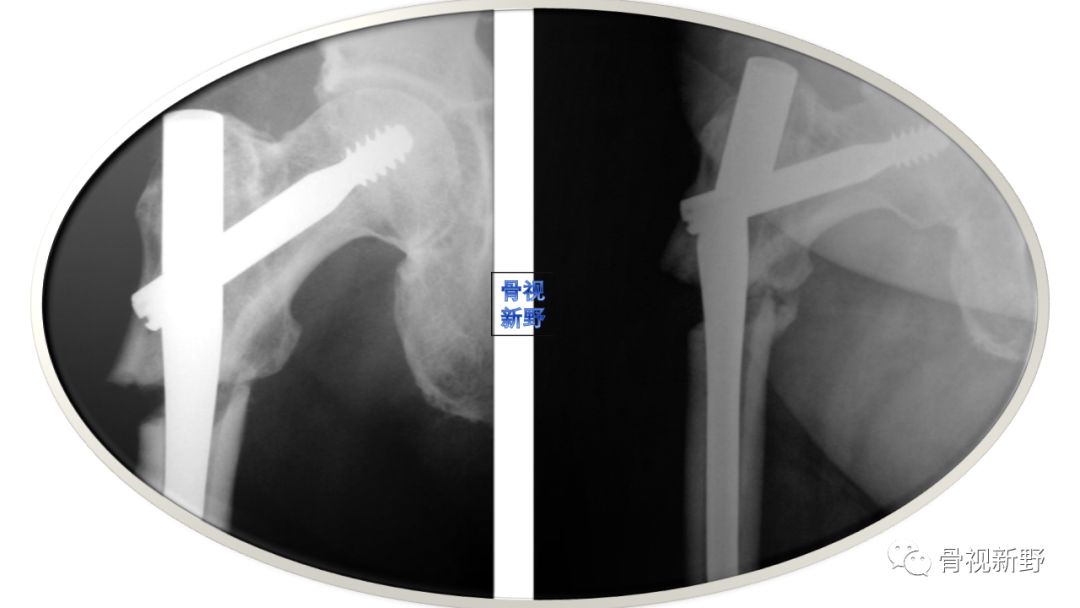

“没有外侧壁,就没有髋螺钉”

累及外侧壁的股骨近端骨折,如反转子及经转子骨折,如果使用滑动髋螺钉,由于缺乏外侧壁的骨性支撑,会发生股骨干向内侧移位及股骨近端骨块向外侧移位。这种移位会导致畸形、骨不连、头钉切出(cutout)。

文献报道反转子骨折用滑动髋螺钉固定的失败率高达56%[Haidukewych GJ 2001]。虽然股骨近端锁定钢板(proximal femoral locking plate,PFLP)、95°角的DCS也可使用,充当外侧皮质的假体,但对更复杂的股骨近端骨折,这些钉板系统并不适合。对反转自骨折,髓内钉较DCS有优势;但髓内钉与PFLP的优、劣对比尚有争议。